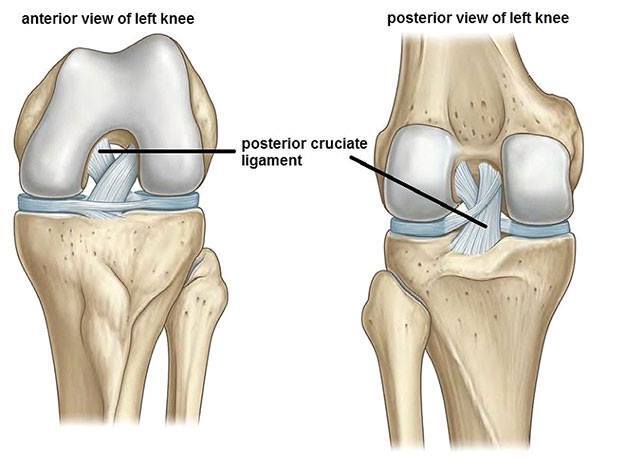

26

Name A-D

A- Suprapatellar bursa B- Prepatellar bursa C- Infrapatellar bursa D- Semimembranous bursa